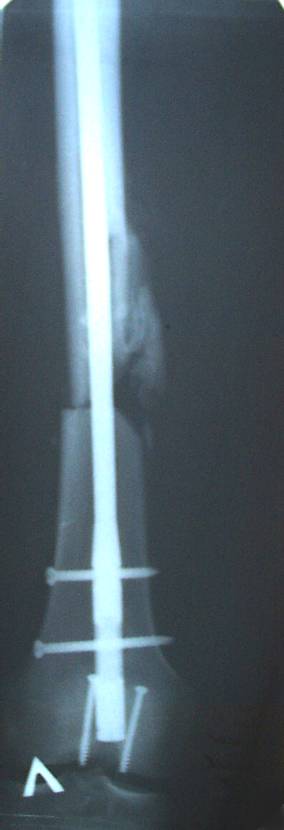

Уважаемый Сергей, избрав вариант DHS плюс ретроградный гвоздь Вы явно обезопасите себя от проблем, связанных с введением штифта через trochanteric fossa. Очень это может быть проблематично, Вы правы. Поэтому DHS плюс ретроградный гвоздь - спокойно выполнимый вариант, особенно в "чужом" отделении. Схожий свой случай из далёкого теперь уже 1999г. прилагаю, только вместо канюлированных винтов у Вас будет DHS (VHS). А если антеградный гвоздь - то только из тех, что предназначены к введению через верхушку вертела. И это тоже выполнимо, но сложнее. Мне так кажется.

Уважаемый Сергей Витальевич! Мы в похожем случае выбрали вариант DHS + DFN. Правда из 4 кортикальных винтов накладки DHS - 2 пришлось вводить монокортикально - уперлись в штифт.. На конечный результат это не повлияло. Ссылка здесь.